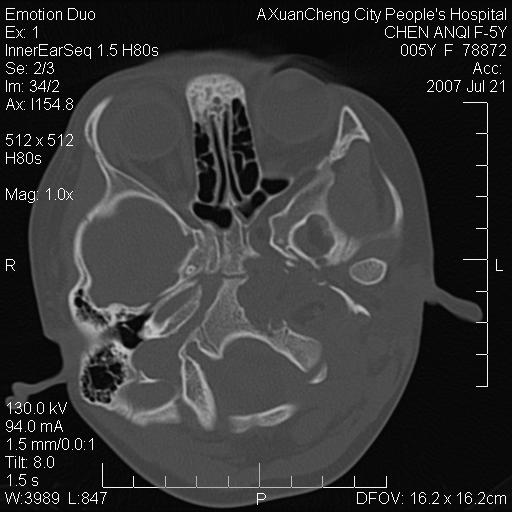

标题: PED0273:5岁,左耳流脓痛疼一周,颅底骨质破坏 [打印本页]

标题: PED0273:5岁,左耳流脓痛疼一周,颅底骨质破坏

患儿5岁,左耳流脓痛疼一周,左外耳道肉芽组织填塞 软组织窗显示病灶内结节状低密度影为气体密度

左侧中耳炎并胆脂瘤,左颞骨岩部骨质破坏并颅内感染积气。

考虑化脓性中耳乳突炎伴胆脂肪瘤形成并左颞叶感染,不除外合并嗜酸性肉芽肿.